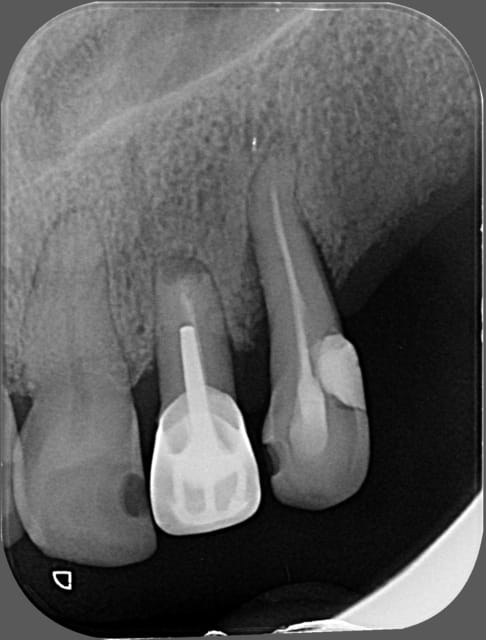

quel serait votre attitude thérapeutique quant aux 45 et 22 ?

en sachant que son opération est prévue le 01/09.

Impossible de donner une réponse définitive sans plus de données, mais rapidement, d'après les radios :

Je laisse 22, le risque est essentiellement mécanique.

Pour 45, si asymptomatique depuis de nombreuses années, je laisse aussi.

Surveillance radiologique bien sûr, et stabilisation occlusale de 23.

patiente diabétique,

aucune symptomatologie bucco-dentaire

sauf que le radiologue qui a fait la pano ( ordo faite par le chir ) note image apicale au niveau de 45 et de 22.